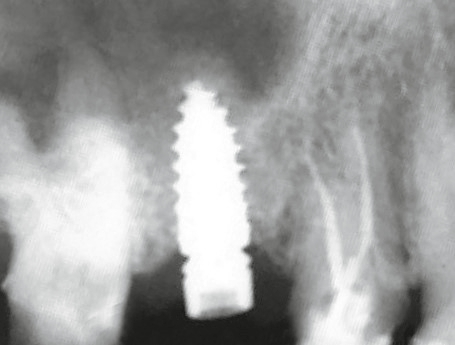

Ob Champions Zirkon-BioWin! (Abb. 9) oder Titan (R)Evolution Implantat (Abb. 11): Das aufbereitete Grinder-Zahnmaterial (Abb. 10) wird beim internen, direkten Sinuslift (IDS) erfolgreich, minimal- invasiv (MIMI Vb) und ohne Komplikationsgefahr mit abgerundeten Condensern und mit linksdrehendem, abgeflachtem 3,7 mm D Krestalbohrer unterhalb der Membran eingebracht.

Der („unblutige“) IDS benötigt nur wenige Minuten. Auf den Kontrollröntgenbildern sieht man deutlich „die Wolken“ des Grinder Materials, welches definitiv zu Knochen umgewandelt wird.